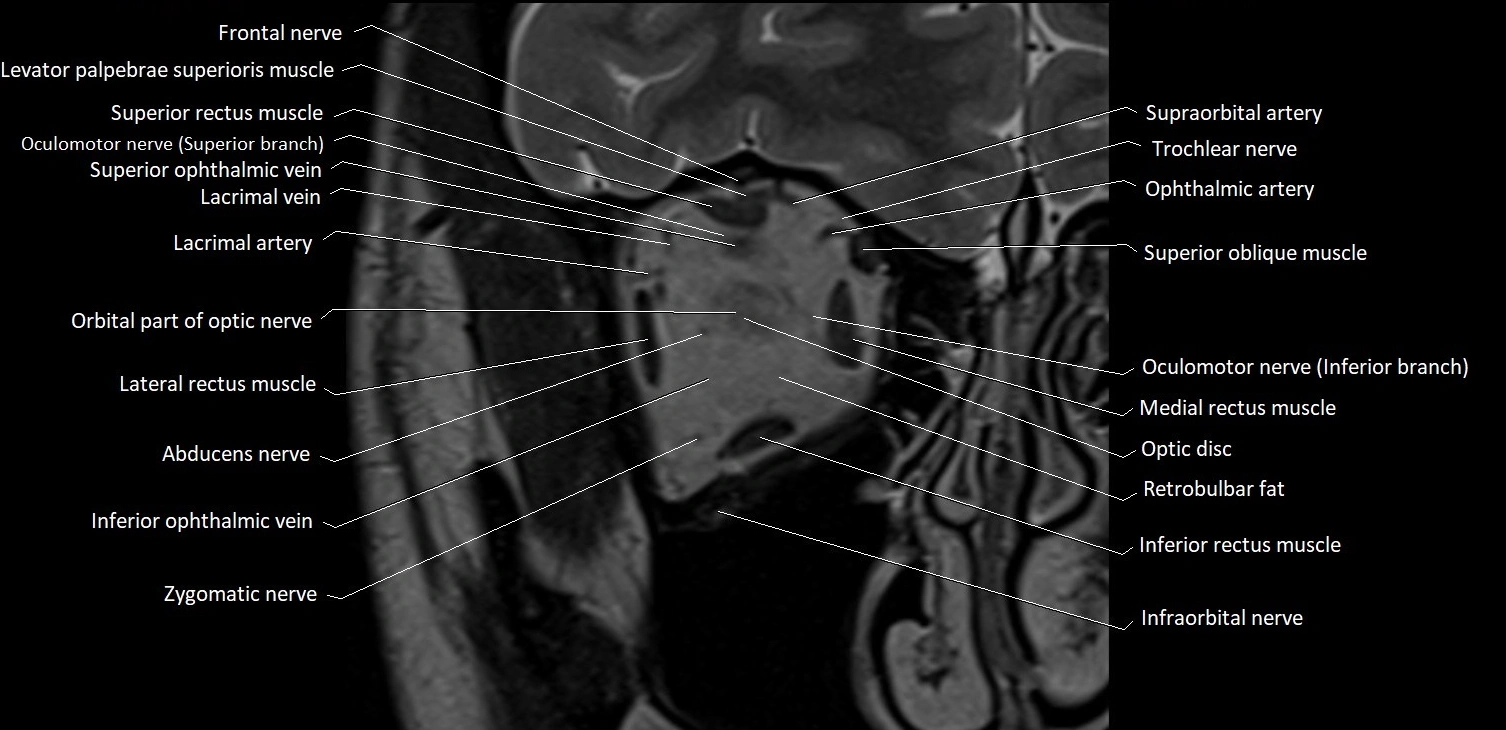

- Abducens nerve (Cranial nerve VI)

- Abducens nerve (orbital part )

- Inferior ophthalmic vein

- Inferior rectus muscle

- Infraorbital nerve

- Lacrimal artery

- Lacrimal vein

- Lateral rectus muscle

- Levator palpebrae superioris muscle

- Medial rectus muscle

- Oculomotor nerve (Superior branch)

- Oculomotor nerve (inferior branch)

- Optic disc

- Orbital part of optic nerve

- Retrobulbar fat

- Superior oblique muscle

- Superior ophthalmic vein

- Superior rectus muscle

- Supraorbital artery

- Trochlear nerve (Cranial nerve IV)

- Zygomatic nerve